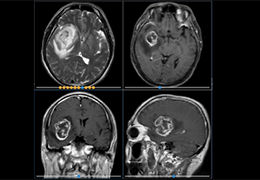

ART-Plan™ Artificial Intelligence Contouring